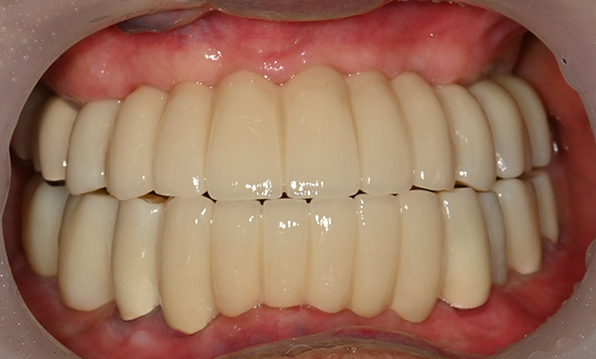

위 아래 치아가 정확하게 맞아야하는 고난이도 임플란트

임상 경험이 많은 숙련된 전문의의 섬세한 기술력이 중요합니다.

치료기간 : 2021.04.12~2021.09.15